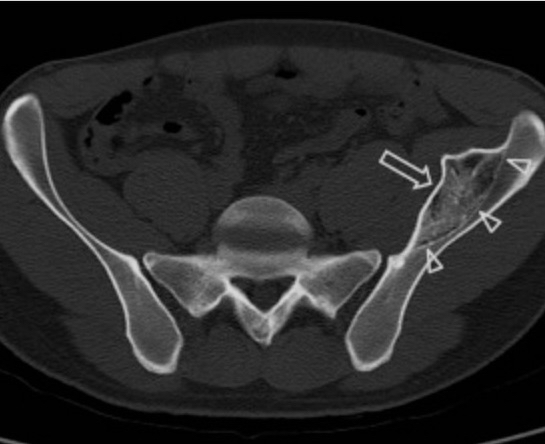

In another case, a young child experienced a direct blow to the orbital bone while watching a match. After some time, the hematoma ossified, forming a very large bony mass at the injury site after 11 months. Scientists reported that the hypertrophy was due to the release of inflammatory factors and the tensile force applied to the periosteum [35]. In another case, a child sustained an injury to the side of the supraorbital area, and similarly, bone hypertrophy was observed at the injury site [36]. Not only that, in another case, a person received a blow to the lower jaw while playing soccer, and after some time, bone formation appeared at the injury site (see figure 6) [37].

(Figure 6: a prominent bony mass in the lower jaw resulting from a direct injury to the mandible during a soccer match)